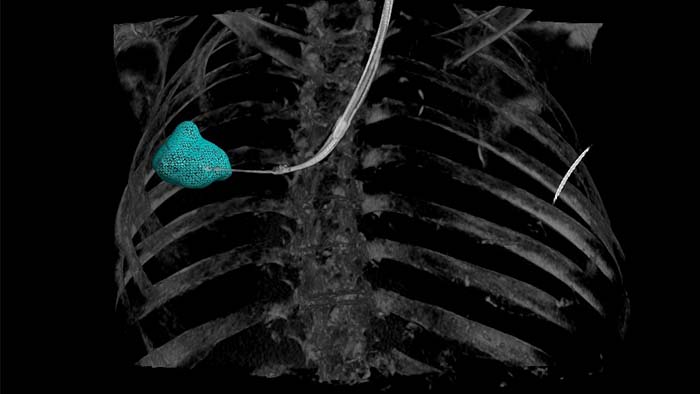

Early detection and treatment are critical to ensure better outcomes and quality of life for lung cancer patients. Today, the majority of patients have to face a long journey to a definitive diagnosis and they often undergo a painful recovery after open surgery. That is why we designed Lung suite, a revolutionary 3D imaging and navigation platform, that supports high precision diagnosis and minimally invasive therapy in one room. Our goal is to shorten the care pathway, improve outcomes and reduce costs. Join us now in this new era for lung cancer care.

The Hybrid OR with a unique design and OR table to easily combine interventional and minimally invasive surgical procedures.

The advanced ceiling-mounted system for cone beam CT bronchoscopy and percutaneous interventions.

The floor-mounted system for cone beam CT bronchoscopy and percutaneous interventions.